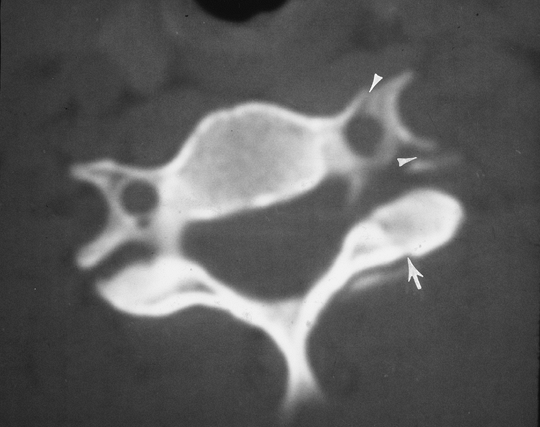

FIGURE 3-16 CT image of a facet fracture (arrow). There is also a fracture through the foramen transversarium (arrowheads).

P.51

![]() |